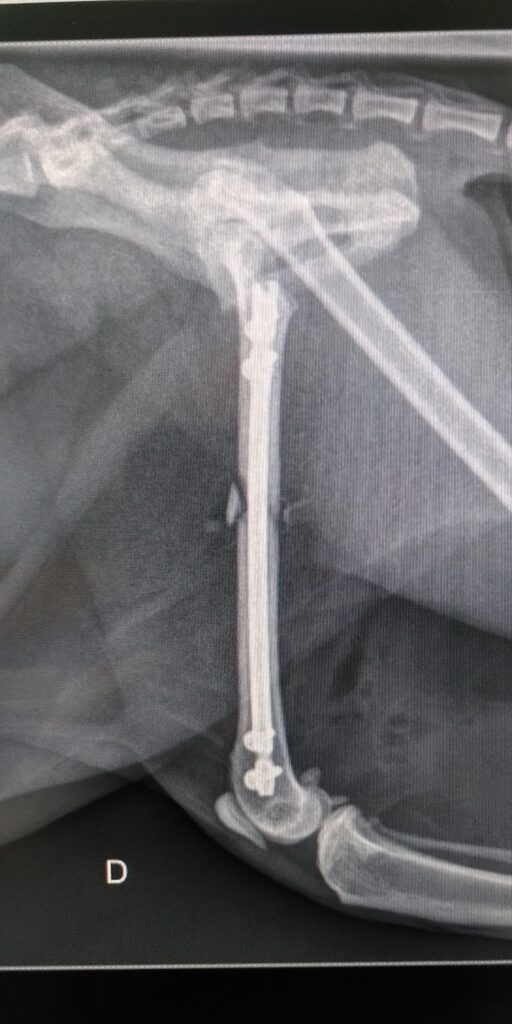

Nous réalisons des TPLO (Tibial Plateau Leveling Osteotomy) pour gérer les ruptures de ligaments croisés du chien, nous stabilisons les fractures d’os long grâce à la mise en place de clous verrouillés, beaucoup plus stable et solide que les anciennes techniques. Nous utilisons les implants ligamentaires et tendineux de dernières générations, permettant de se passer d’immobilisation post opératoire dans la majorité des cas.